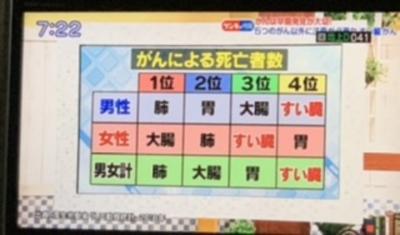

齢77血糖値異常?!癌が見つかった、即外科削除!

- 伏見

- 2020/10/20 - 2020/11/06 4

- エリアの満足度:0.0

- travelの友達も、定期検査で予防と最低限の治療を!原稿寿命だから、楽しめる国内外の散策ですから! CORONA禍に良く見つかった私の癌細胞!術前の造影画像や......もっと見る(写真16枚)

見つかっちゃった!ガン細胞、オペ入院!

- 伏見

- 2020/10/16 - 2020/10/16 4

- エリアの満足度:0.0

- まさか!CORONA禍に癌の早期発見!齢77 開腹手術へのアプローチ!終いの初めての入院、生かされて!メディカル機器の進化!久しぶりの聴診器!術後回復へのチャレ......もっと見る(写真46枚)